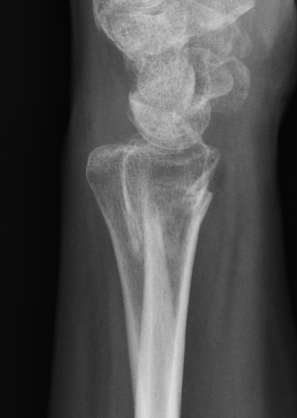

Xray

Bilateral xrays

PA film in neutral

- wrist neutral

- elbow & shoulder at 90°

CT

Malunion

| Radial shortening | Radial inclination | Positive ulna variance |

| Dorsal tilt > 15 degrees | Volar tilt > 10 degrees | Articular step > 3 mm |